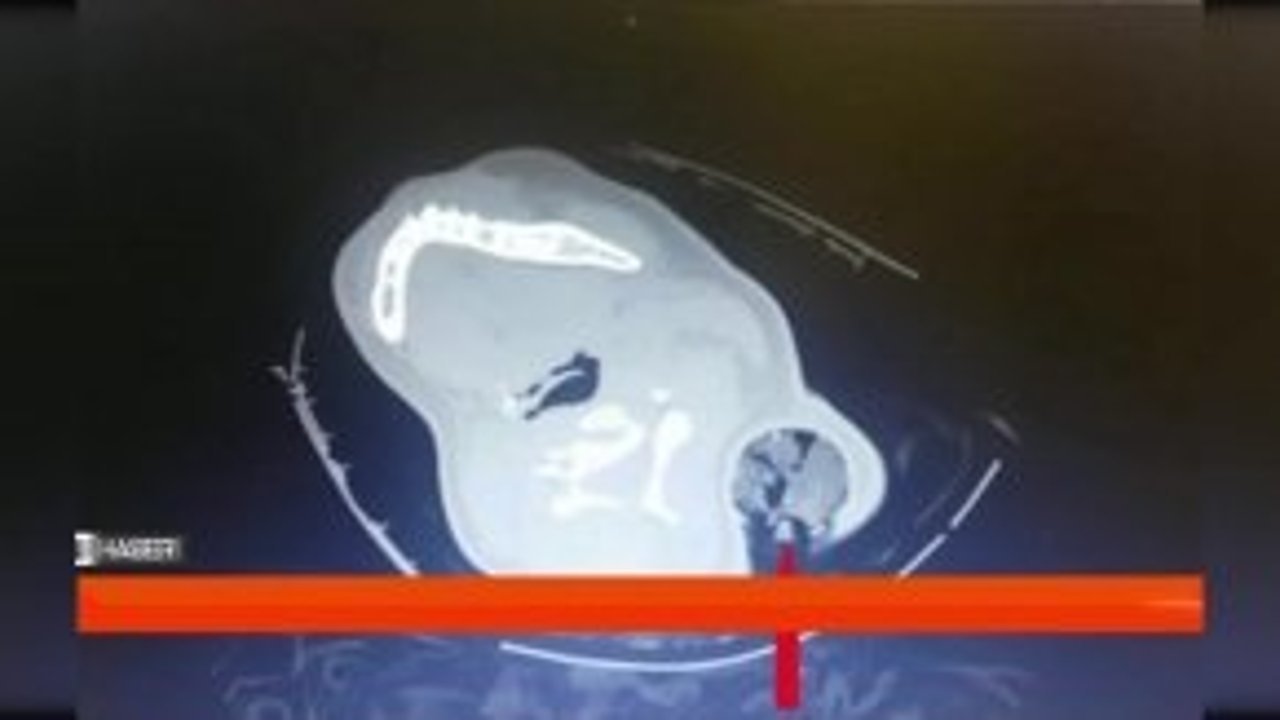

Kahramanmaraş’ın Pazarcık ilçesinde gerçekleşen trafik kazasında 19 yaşındaki kızın boynundan girip koltukaltından çıkan 30 santimetrelik kazık, Kahramanmaraş sütçü imam üniversitesi (ksü) sağlık uygulama ve araştırma hastanesinde (ksü tıp) gerçekleştirilen başarılı...